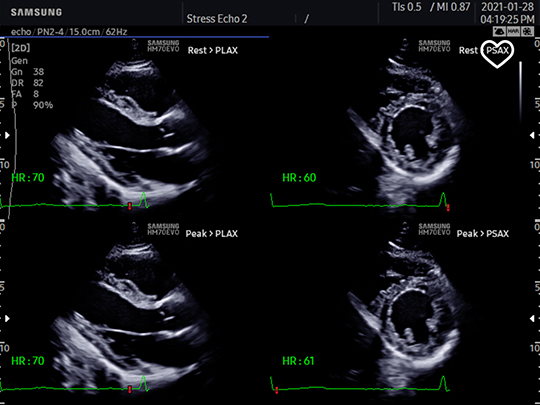

PN2-4

- Application: abdomen, cardiac, vascular, pediatric, TCD